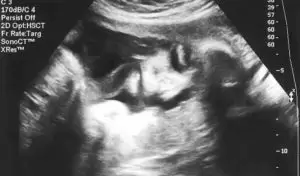

Gebeliğiniz sırasında olabilecek bazı gelişmeler hemen dikkate alınmalıdır. Unutmayın, size tanı koyacak ve tedavinizi düzenleyecek tek

Gebelik sürecinde çeşitli rahatsızlıklarınız olacak, dönem dönem şikayetleriniz artacaktır. Bu yazımızda hamilelik döneminde ne gibi